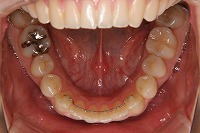

下顎

上の前歯が出ている事を主訴に来院された、23歳2か月の女性です。診断「下顎骨の後方回転による骨格性上顎前突で開咬を伴う」上顎は両側第1小臼歯、下顎は抜歯をせず治療を行いました。